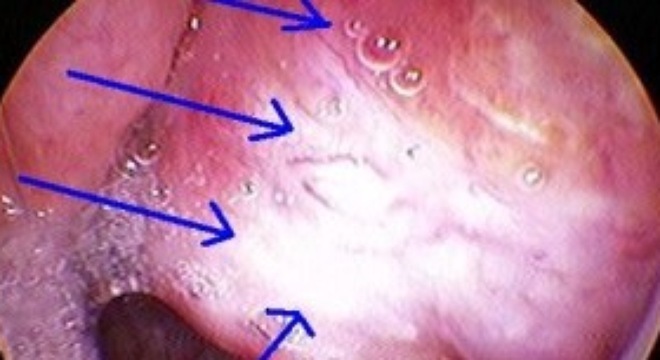

Ung thư vòm họng là căn bệnh ác tính xuất hiện khi một hoặc một vài tế bào biểu mô trong vòm họng bị biến đổi gen, tạo thành khối u trong vòm họng.

Ung thư vòm họng là căn bệnh rất nguy hiểm vì có diễn biến nhanh nhưng lại rất khó phát hiện gây khó khăn rất lớn cho việc điều trị.